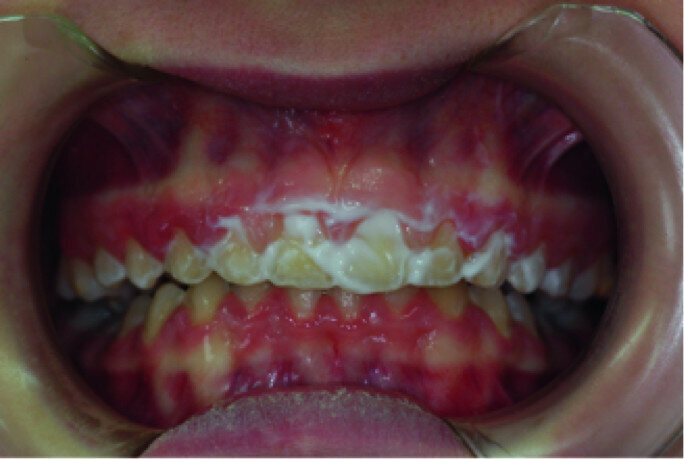

Clinical view, showing gingival enlargement, just before the debonding procedure.

A 14-year-old female patient was referred to our department by the orthodontics unit because, at the end of fixed orthodontic treatment, she had developed gingival enlargement in the upper arch (Fig. 1), probably related to the fast closure of the spaces associated with very poor oral hygiene due to bleeding during toothbrushing. Just after the removal of the appliance, a topical anaesthetic (EMLA, AstraZeneca) was applied to the gingivae (Fig. 2) and a gingivectomy was performed using a diode laser (XD-2, Fotona) according to the technique of removal of the inter dental papillae (Fig. 3). The parameters used were as follows: a wavelength of 808 nm, 3 W in continuous wave, a 320 μm fibre in contact mode. The intervention had a duration of 375 seconds, and the patient did not feel any pain (Fig. 4). After the intervention, the patient did not take any kind of pain medication, and the healing process was completed in five days (Fig. 5).